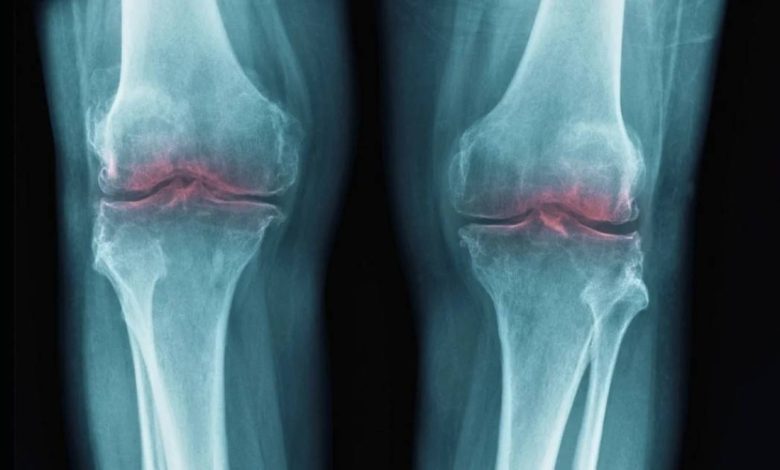

يرتبط هذا البروتين بشكل واسع بعمليات الشيخوخة، إذ يزداد تركيزه مع التقدم في العمر، ويؤثر سلباً على الجزيئات المسؤولة عن إصلاح الأنسجة وتقليل الالتهاب، هذا ما دفع باحثين من جامعة ستانفورد إلى دراسة دوره المحتمل في تدهور المفاصل، خاصة أن التهاب المفاصل يحدث نتيجة تحلل الكولاجين في الغضروف، ما يؤدي إلى الألم والالتهاب وتقييد الحركة.

في تجارب أجريت على فئران مسنة، لاحظ الباحثون أن تثبيط إنزيم 15-PGDH أدى إلى زيادة سماكة غضروف الركبة الذي كان قد تآكل سابقاً وفق sciencealert.

وعند إحداث إصابة مشابهة لتمزق الرباط الصليبي الأمامي لدى الفئران، ثم تطبيق العلاج، لم يتطور المرض كما هو معتاد، ما يشير إلى تأثير وقائي قوي، وقد أظهرت صور الفحص أن الغضروف المعالج في الفئران الأكبر سناً أصبح أقرب في بنيته إلى الغضروف الشاب السليم، من حيث الكثافة والمرونة.